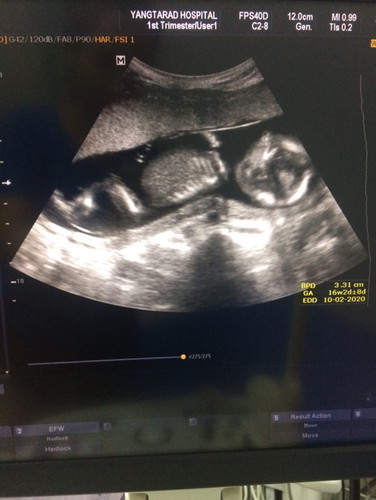

กำหนดคลอด กุมภา 63 คะ แม่บ้านไหนกำหนด 63เหมือนกันบ้างคะ 15 w พอดีคะ

25/2/63จร้า 16+6วีคล่ะค่ะ